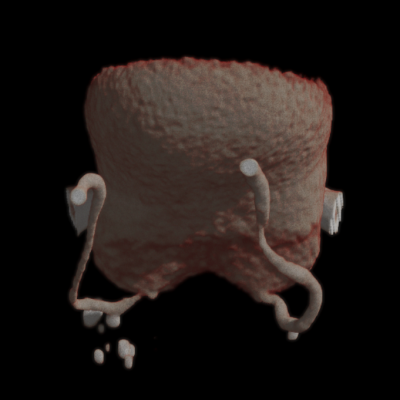

Тубооваріальне утворення додатків матки.

Відмежований хронічний тазовий перитоніт.

Лапароскопія. Видалення запального тубооваріального утворення додатків матки в умовах відмежованого хронічного тазового перитоніту. Санація черевної порожнини.